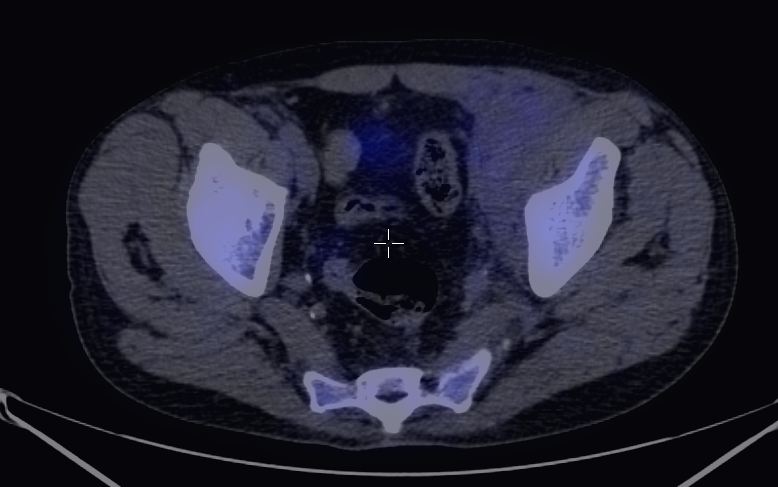

More complex anatomic structures (spine, the base of the skull, facial and hip bones) can be imaged more confidently with SPECT scans. On one hand, they provide a more accurate spatial localization and on the other, with their superior contrast resolution, they are able to differentiate lesions even if planar exams are negative or uncertain. SPECT-CT can characterize the CT morphology of the lesions with pathologic uptake. Thus, it is capable to provide a definitive diagnosis. (Figure 4.)

Image

a

b

c

d

e

4. Bone scintigraphy, prostate cancer. The image set shows the characterization of multiplex increased activity uptake. Posterior whole body scan (a). SPECT-CT coronal fusion images (b,d), CT examination (c,e). Sclerotic lesions in the pelvic bones are suggestive of osteoplastic metastases (b,c), small joint arthrosis at LIII-IV segments, more expressed on the left side (b,c), spondylosis on the right side at LIV-V segments (d,e). (The increased activity spot on the whole body scan, at the left cubital region, is correspondent to the paravasation of the iv. radiopharmaceutical.)